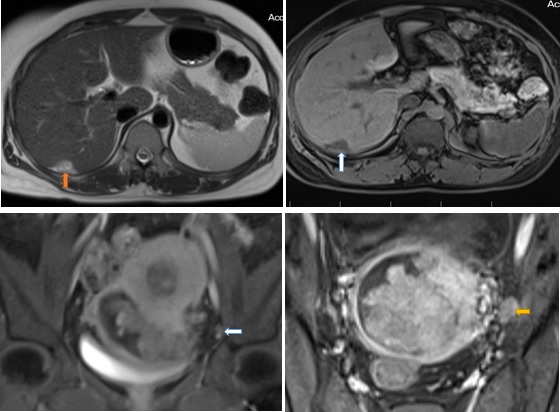

Kết quả MRI: Từ buồng nội mạc lan tới âm đạo có khối choán chỗ kích thước # 68 x 86 x 72 mm (trước sau- cao -ngang), tín hiệu trung gian trên T2W, thấp trên T1W, hạn chế khuếch tán, bờ ngoài u không đều, đa thuỳ, u xâm lấn không thấy cổ tử cung. U có cuống xuất phát từ vùng đáy tử cung. Sau tiêm Gd, u bắt thuốc tương phản mạnh không đồng nhất. Dọc vách chậu hai bên có vài hạch hình tròn kích thước # 9 x 15 mm, bờ ngoài không đều, bắt thuốc tương phản kém. Rải rác phúc mạc vùng chậu có vài nốt bất thường tín hiệu kích thước </= 17 x 22 x 15 mm, bờ đa cung, hạn chế khuếch tán, bắt thuốc tương phản không đồng nhất.Vùng phía sau gan ngay hạ phân thuỳ VIII có nốt bất thường tín hiệu kích thước # 27 x 20 mm, tín hiệu trung gian trên T2, thấp trên T1, bắt thuốc tương phản kém sau tiêm, khối này ấn lãm bờ gan

Kết luận: Hình ảnh gợi ý sarcoma cơ tử cung xâm lấn cổ tử cung. Chẩn đoán phân biệt: Ung thư nội mạc tử cung giai đoạn IVB (FIGO), hạch vách chậu hai bên dạng hạch di căn, nốt phúc mạc vùng chậu nốt ở sau gan phải ấn lõm bờ gan nghĩ mô u reo rắc

Hình 4: Hình trên trái T2W sagital thấy khối từ lòng tử cung lan xuống cổ tử cung, xâm lấn cơ vùng cổ tử cung. tổn thương có tín hiệu cao nhẹ không đồng nhất trên T2W (ngôi sao trắng). Hình trên phải, T1 FS trên măt cắt ngang thấy tổn thương tín hiệu giống cơ vùng cổ tử cung, không rõ ranh giới giữa tổn thương và cơ vùng cổ tử cung (ngôi sao xanh) . Hình dưới bên trái: sagital T1 FS sau tiêm Gd, tổn thương bắt thuốc tương phản mạnh không đồng nhất (ngôi sao đen). Hinh dưới phải: T1 FS coronal sau tiêm tổn thương bắt thuốc tương phản mạnh không đồng nhất ( ngôi sao vàng)

Hình 5: Hình trên trái: nốt reo rắc phúc mạc bờ gan hạ phân thùy VII, tín hiệu cao nhẹ trên T2 ( mũi tên cam); hình trên phải: sau tiêm Gd trên xung T1 vibe FS tổn thương bắt thuốc tương phản kém ( mũi tên trắng) ; Hình dưới trái: Nốt bắt thuốc phúc mạc vùng chậu trên hình T1 vibe FS sau tiêm Gd ( mũi tên trắng); Hình dưới phải: T1 FS Sau tiêm Gd hạch bắt thuốc tương phản không đồng nhất (mũi tên vàng)